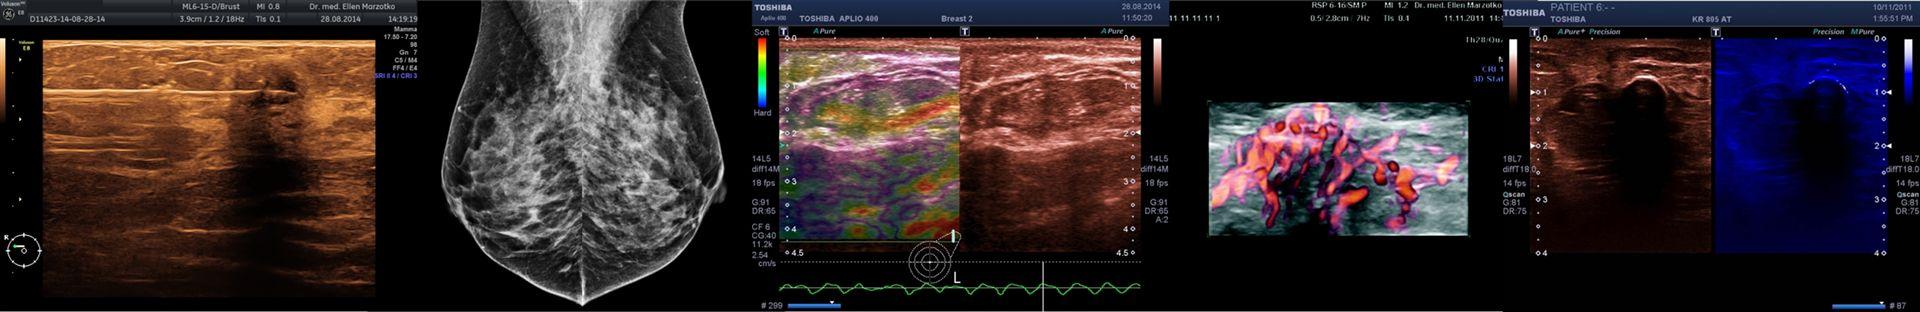

Der hochauflösende Ultraschall der Brust ist ein unverzichtbarer Bestandteil der Diagnostik von Erkrankungen der weiblichen Brust. Eine präzise moderne Bildgebung durch einen erfahrenen und verantwortungsbewussten Arzt ist die Basis der Früherkennung, Ausbreitungsdiagnostik und auch der Nachsorge von Brustkrebs.